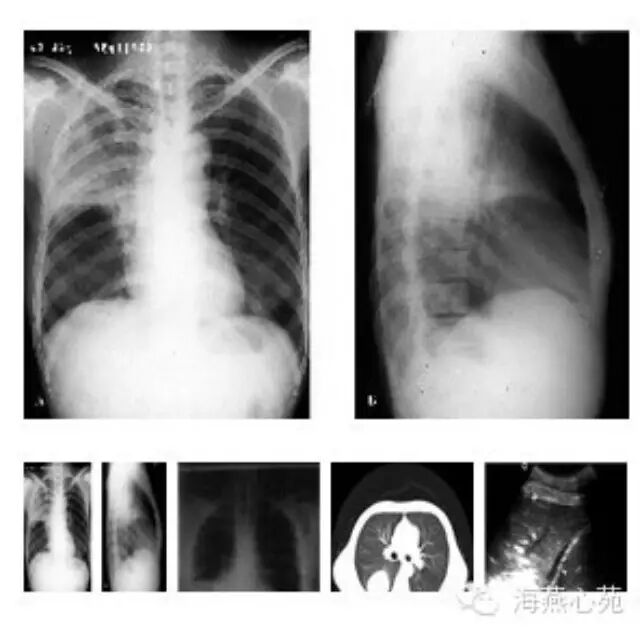

其实,任何细菌均可引起大叶性肺炎,比如支原体、肺炎链球菌、溶血性链球菌等等。大叶性肺炎是以肺泡内弥漫性纤维素渗出为主的急性炎症,起病较急,病变起始于局部肺泡,并迅速蔓延至一个肺段或整个大叶。患儿可表现为高热,通常可在39度以上;剧烈的咳嗽,有的患儿干咳,有的咳嗽时有痰;恶寒;厌食;嗜睡,精神状态差;部分患儿有恶心、呕吐、腹泻等胃肠道反应;还有个别患儿症状不典型,长期咳嗽。重症患儿可有呼吸困难甚至并发感染性休克。

我们人体共有五个肺叶,大叶性肺炎是某个肺叶整个发生病变,常合并胸膜炎、胸腔积液,如不及时治疗会危及生命。受累肺组织坏死液化可形成肺脓肿,当胸膜病变严重时可发展成纤维素性化脓性胸膜炎,甚至脓胸。如果炎症没有及时清除,还可机化,最后堵塞支气管,导致肺不张。当孩子出现肺不张后,常常气短,活动受限。